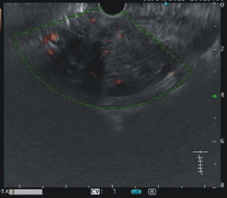

圖二、顯示傳統的內視鏡超音波偵測病灶血流的能力不儘理想

圖三、顯示對比增強諧波內視鏡超音波(Contrast-enhanced harmonic EUS)可以凸顯病灶血流豐富的程度(畫面右邊變的較亮)